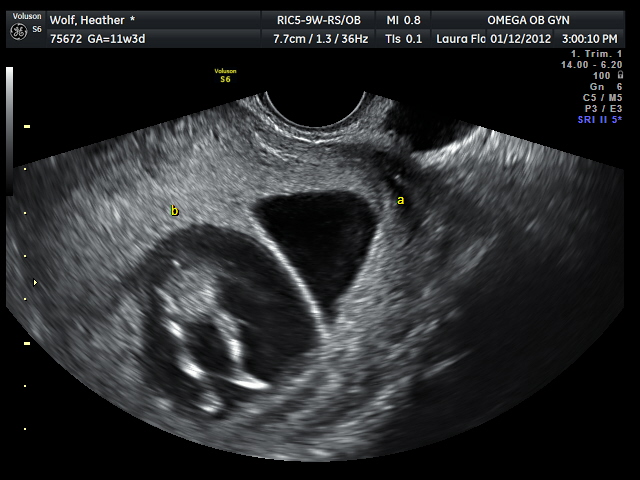

| They're getting big enough that they don't fit one screen together - although we got a quick shot here. (I think a head and a behind with legs but not 100% sure) |